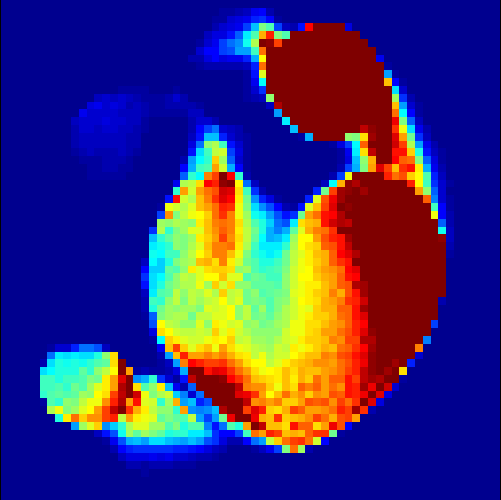

The first data set consists of a heart-shaped region and three circles on a static background (see figure 1 (a)). The two smaller circles are assumed to belong to

the same tissue type and therefore to the same subregion, which causes a total of four subregions, including the background. To simulate a more realistic application of dynamic SPECT

imaging, we used a synthesized representation of a rat liver as a second data set (see figure 1 (b)). The temporal concentration curves used to simulate the data sets

are shown in figure 2. As before, the total number of subregions was chosen to be equal to four in order to provide a both simple and realistic shape model.

In a first test, every image sequence was reconstructed out of the exact given sinograms. Additionally we tested noise corrupted data by first scaling the sinogram by a parameter , corrupting them with Poisson noise via the MATLAB imaging toolbox command imnoise and finally rescaling the image to the original range (see figure 4). The average count number per time step (i.e. the average of the discrete -norm of the data at each time step) is approximately in case of the heart-shaped data set and ca. in case of the rat liver simulation. The results at a certain number of time steps can be seen in figure 6 and 7. For comparison, we additionally performed a reconstruction with a simple alternating EM method, keeping the assumption that the tracer can be modelled as a sum of indicator functions and subconcentration curves, but neglecting any regularization terms. In all tests, the outer iteration number was set to 1000 with 10000 inner iterations per subproblem, to obtain a result within a reasonable time period. As stopping criterion, we chose the primal dual residual (cp. [12]) for the inner and the maximum over the Frobenius norms of and for the outer iterations. The results are displayed in 6 and 7 respectively.

As one can see in both figures, the reconstruction method applied to each data set performs very well, especially in contrast to the simple alternating EM method. This clearly shows the benefits of the proposed regularization methods. In case of noise-free given data, the shape of every object, where especially the heart is of higher interest, is clearly defined. As expected, we often observe errors in the edges of each region and where two regions are directly connected (the heart and the upper left circle). This causes the algorithm to incorrectly assign these pixels to another region. Furthermore, the reconstruction difficulties increase with an increase in noise. Some more pixels are assigned to the wrong region, which leads to a small hole-like structure within the heart region and causes a slight blurring effect. In the second data set the method clearly outperforms several other approaches by providing very clearly defined regions and even reconstructing fine structures of the phantom. However, as mentioned before, a clear reconstruction of the rat liver required highly optimized parameter sets, which makes the whole problem quite susceptible to parameter changes.